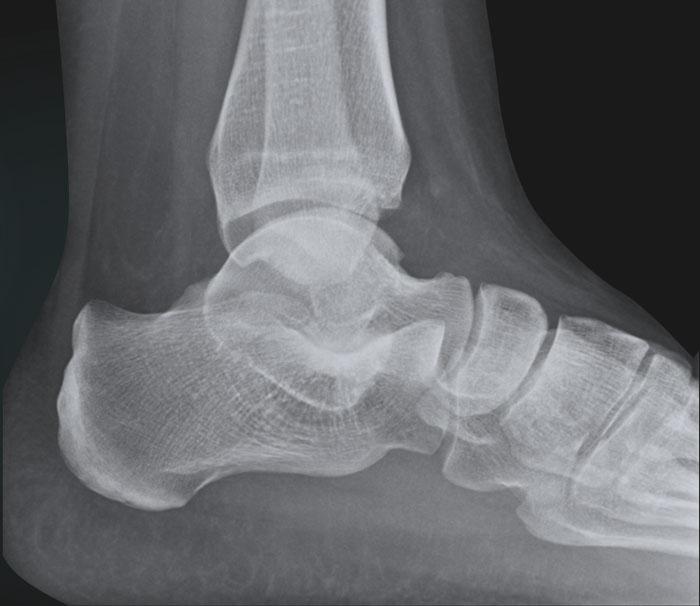

Ca 2 – Đau mạn tính

Bé gái 17 tuổi bị đau mạn tính vùng cổ chân và bàn chân.

Bệnh nhân có tiền sử bong gân cổ chân tái phát nhiều lần.

Hình ảnh cho thấy những dấu hiệu gì?

Nhấp vào hình ảnh để xem phóng to.